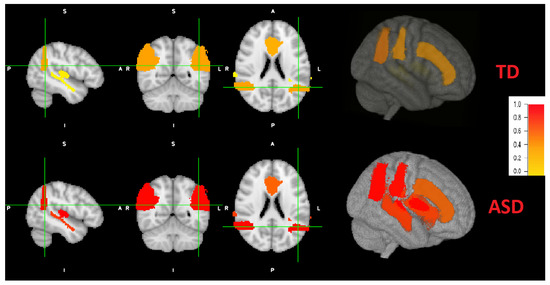

Figure 8.

Coronal, sagital and axial 2D views and a 3D view of both ASD and TD example. Brain areas for the ASD individual are more severely distributed (red highlights) than TD peer (more yellow highlight distribution).

Figure 8 also demonstrates a 3D view. The viewing tool is FSLeyes through FSL. As can be noted, the grade of autism are higher (red colors) of ASD subjects, with variable grade on each area. The grade of autism for TD subjects is lower (yellow colors) with different grades.